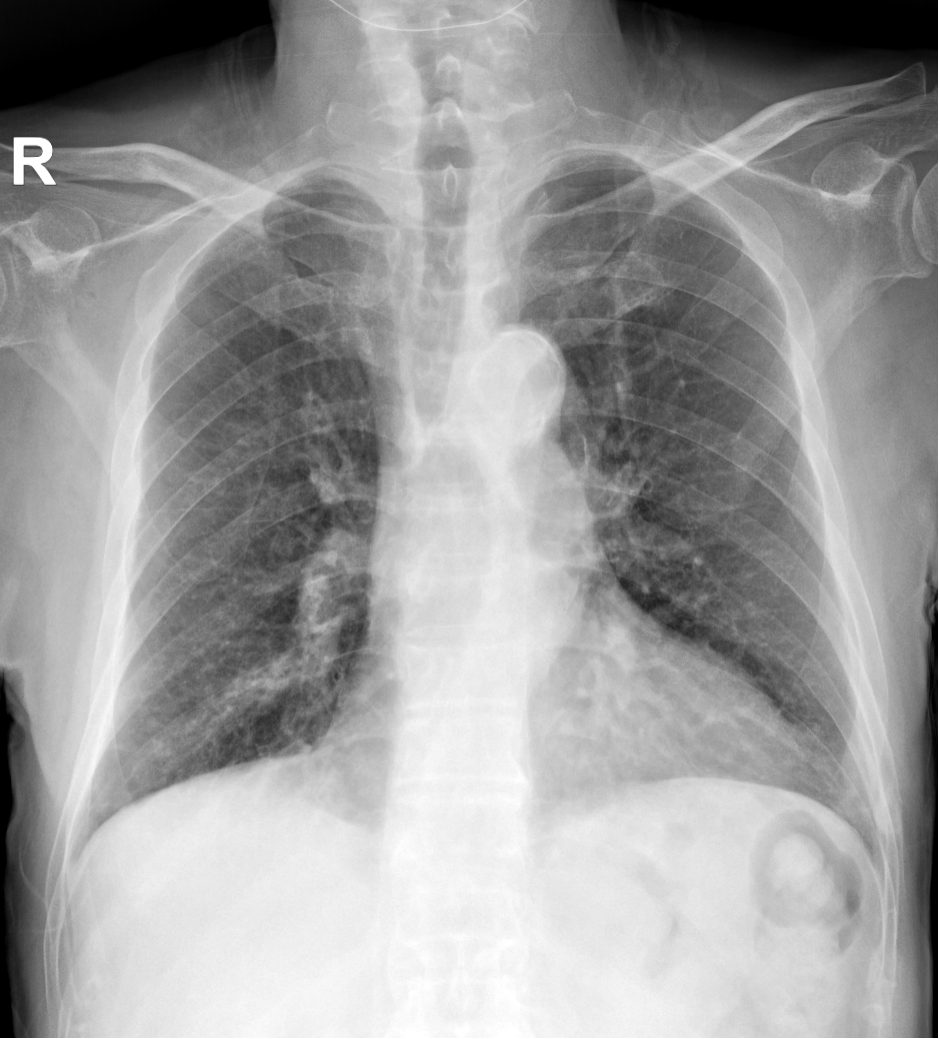

以上为同一位患者x光片。左图为床边拍片,右图为放射科固定机房设备拍摄的胸片,两图的清晰度及对病变的显示有区别。